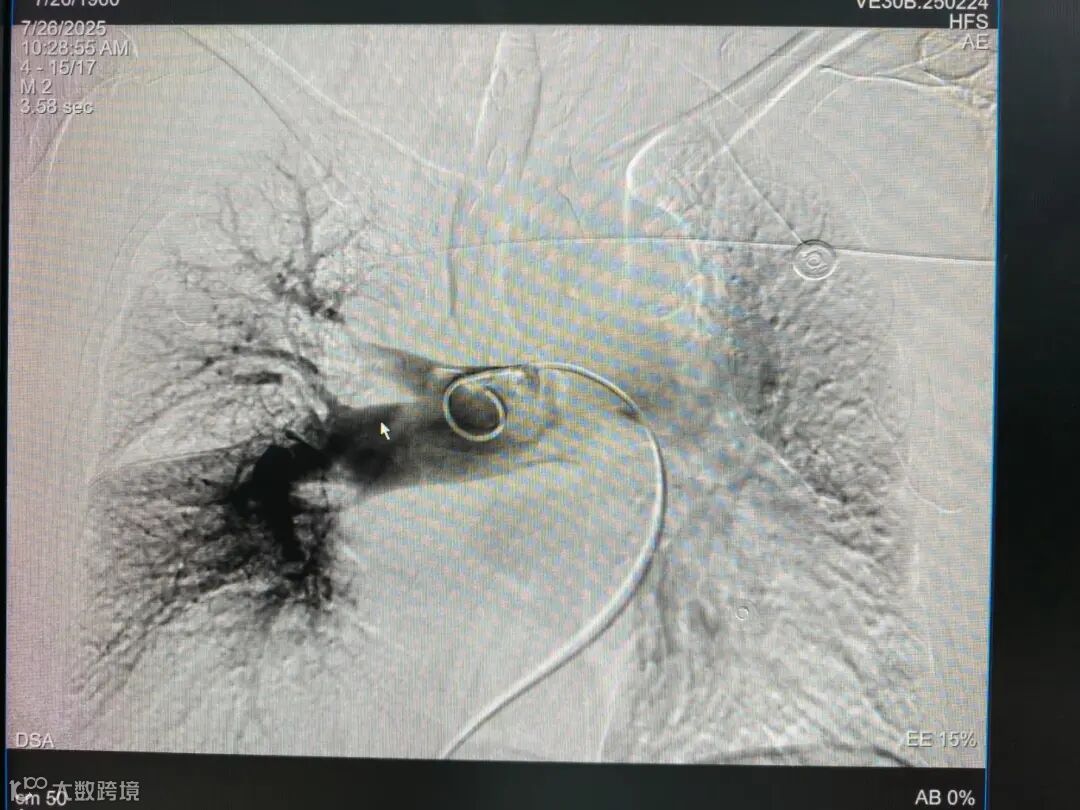

术中建立通路,抽吸导管沿超硬导丝送至右肺动脉,管口贴近血栓处停止,撤出内芯,将Tendvia®取栓支架沿导丝通过抽吸导管向前推送,再回撤输送鞘,支架自动打开,连接负压抽吸器(60ml专用大注射器),回撤取栓支架的同时旋转开关释放负压,血栓在支架及负压的作用下进入抽吸导管中并被带出体外。

取栓中